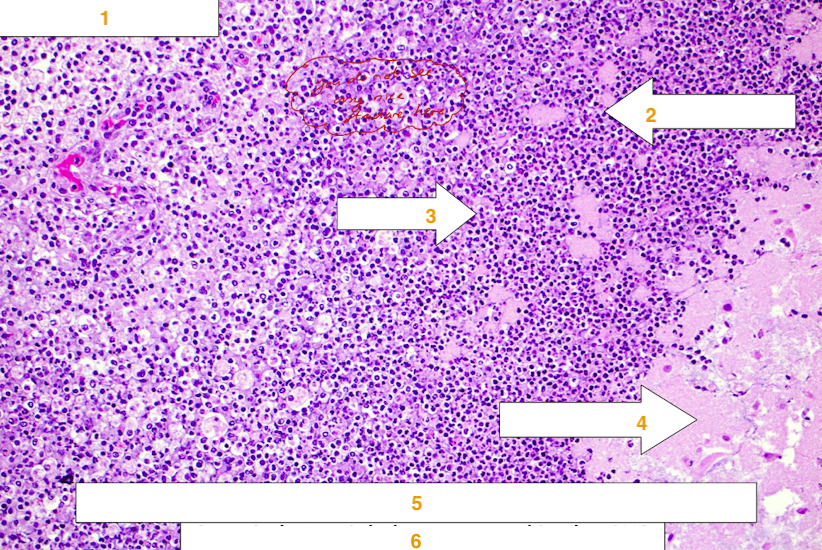

Name the type of necrosis that is present on the histological slide below:

caseous necrosis